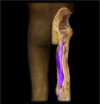

Iliotibial (IT) band

Vastus lateralis

(Femoral n.)

Ext of knee